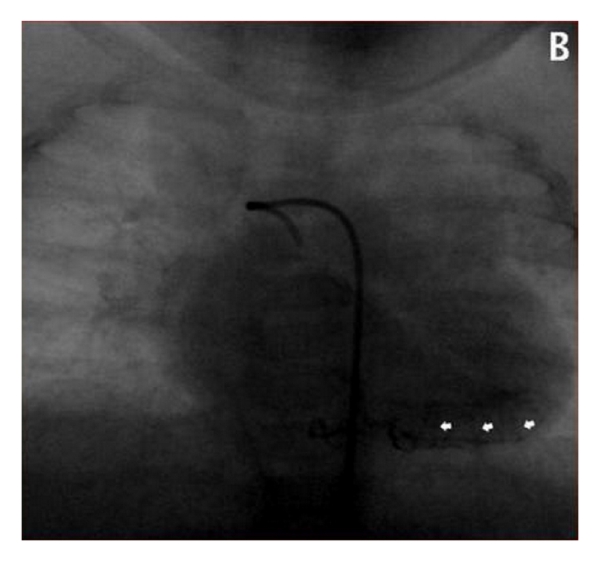

The left coronary artery was mildly dilated with an ostial diameter of 3.8 mm. Additionally, the patient manifested multiple small ventricular septal defects, as well as haemodynamically unsignificant patent ductus arteriosus and patent foramen ovale. The valves were normal. An angiogram performed at 4 months of age confirmed the above findings (Figure 1(b)).

Conclusively, the patient exhibited a complex cardiopathy, encompassing multiple coronary artery microfistulas, mild dilatation of the left coronary artery, ventricular and atrial septal defects, and patent ductus arteriosus. Nevertheless, she was asymptomatic and required no pharmaceutical or interventional therapy.